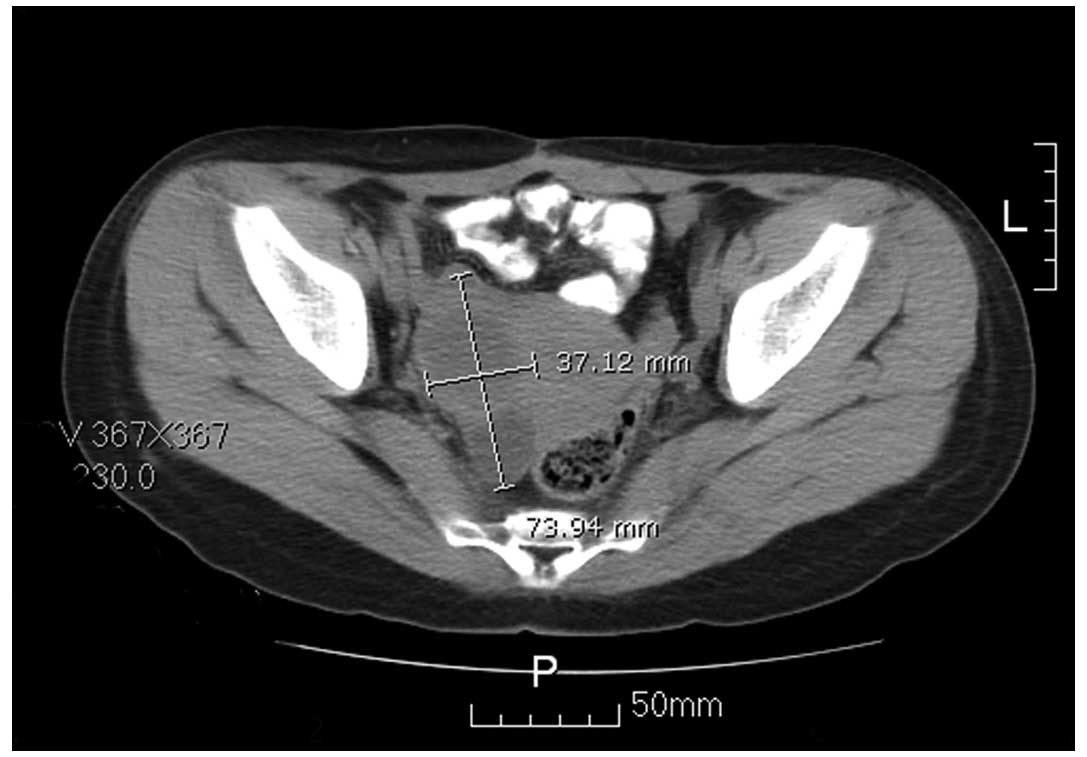

However, tumor recurrence occurred just three months following the final BVP regimen. The serum AFP level elevated to 72.80 ng/ml on January 10, 2011 and the CT scan revealed that the cystic and solid mass in the right parametrium had markedly increased (compared with the prior MRI) (Fig. 6). Radical surgery (hysterectomy, unilateral right side salpingo-oophorectomy and right pelvic lymphadenectomy) was performed on January 18, 2011. No residual tumor was found and the histopathology report showed spindle cells (although a YST was initially considered) on the surface of the small intestine (Fig. 7).

Figure 6

Computed tomography revealed the cystic and solid mass in the right parametrium markedly increased (measuring 3.7×7.3 cm).